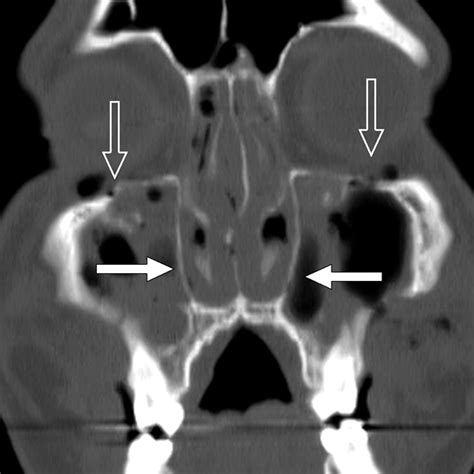

The classification system developed by René Le Fort remains the gold standard for describing patterns of maxillary fractures. While a Lefort I fracture affects the lower maxilla and a Lefort II involves the mid-maxilla and nose, the Lefort III fracture is defined by a transverse fracture line that traverses the frontozygomatic suture, the orbit, and the nasofrontal suture. Essentially, the entire facial skeleton is disconnected from the skull, creating a "floating" midface.

Due to the complexity of these injuries, patients often present with a characteristic "dish-face" deformity, where the middle of the face appears sunken or pushed backward. The diagnostic process is rigorous, often requiring high-resolution CT scans to map the displacement of bone fragments precisely before surgical planning can begin.

Clinical evaluation of a potential Lefort III fracture requires a systematic approach. Physicians look for specific signs, including airway obstruction, massive facial swelling, and malocclusion, where the upper and lower teeth fail to align correctly. The following table summarizes the key clinical indicators often associated with these high-impact facial injuries:

Periorbital Ecchymosis "Raccoon eyes" caused by basal skull or orbital fractures.

• Ocular Damage: Because the fracture line runs through the orbit, vision changes, extraocular muscle entrapment, or nerve damage may occur.